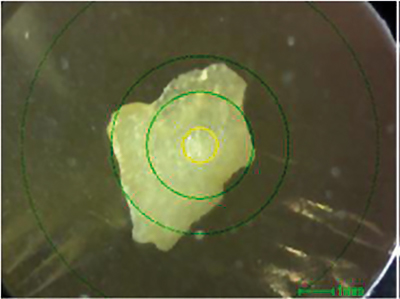

In a first step, a human tooth was analysed. Figure 1 shows a photograph of the contaminant, and Figure 2 shows a qualitative and quantitative analysis by ED-XRF. Calcium (Ca) and phosphorus (P), which are the main components of teeth, could be confirmed. Although the elemental composition is similar to that of bone, the lower content of strontium (Sr) is a characteristic feature of teeth. Like calcium, strontium is an alkaline earth metal and, therefore, can also be used to build teeth.

Figure 1. Photograph of contaminant (the yellow circle is the x-ray irradiation range: 1 mm ⌀).